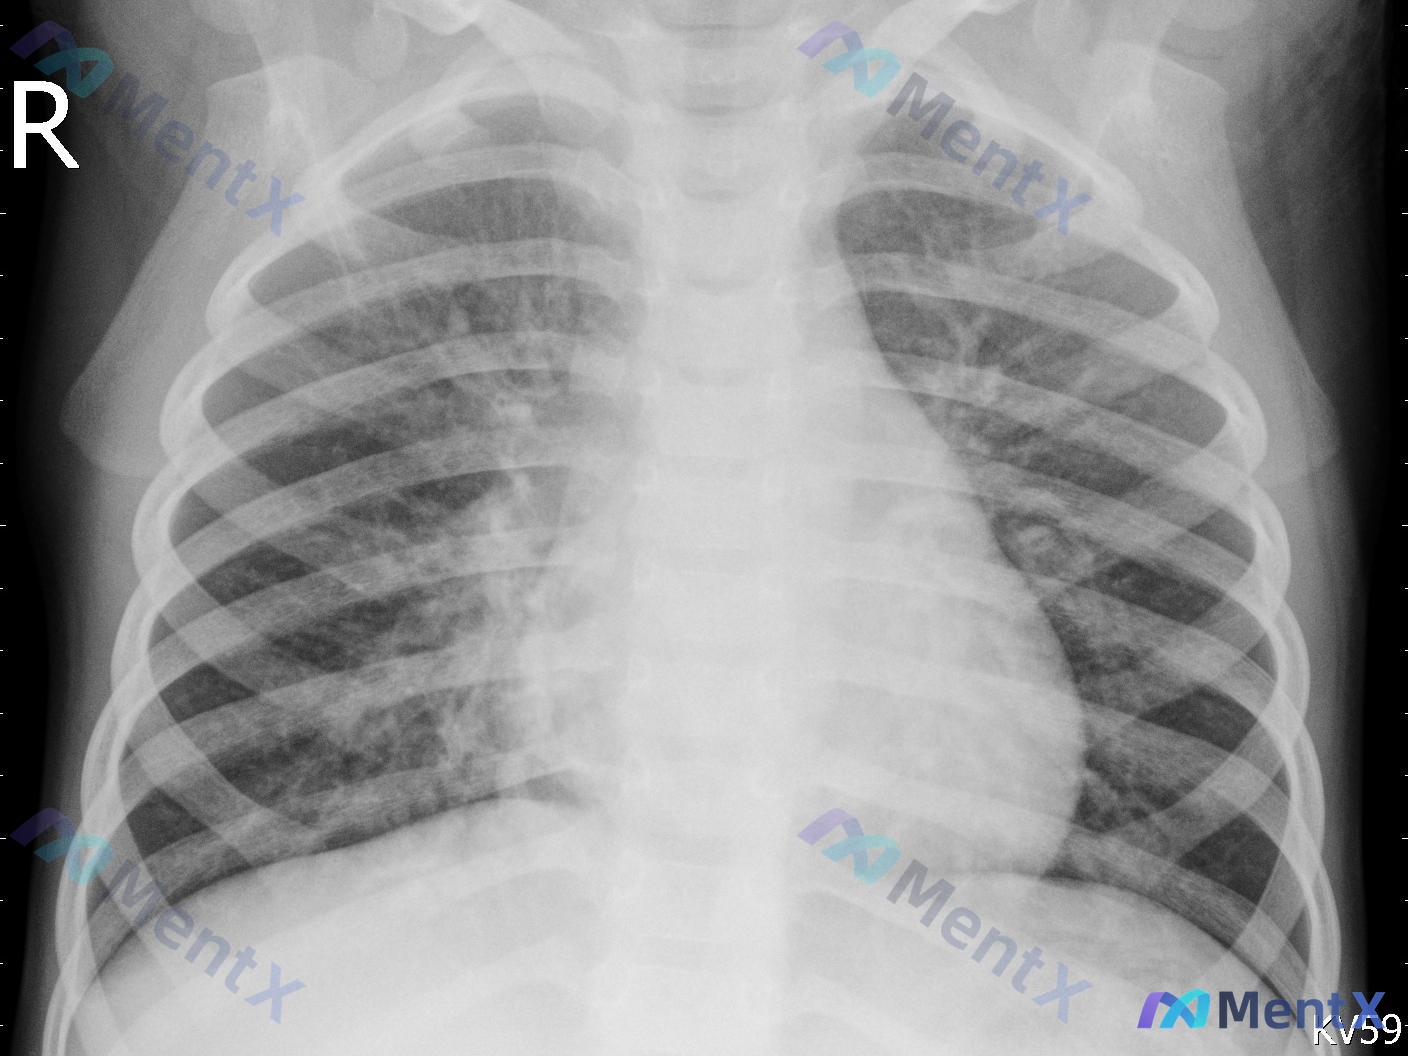

整理到一张儿科胸部正位X光片,先放客观影像表现,大家第一眼会怎么考虑? 基础情况:儿科,前后位(AP)投照 影像所见: - 气管居中,心影大小形态大致正常 - 双肺纹理增多、增粗、走行紊乱 - 双肺野(尤其右侧中下肺野及左侧中下肺野)可见散在模糊斑片状密度增高影 - 双侧肺门影稍显模糊,肋膈角清晰,...

整理了一份儿科胸部正位X光片的病例资料,影像表现和分析方向都比较有讨论价值: 基础影像背景: - 患儿是儿科人群,投照体位是仰卧位前后位(AP位) - 曝光适中,能看清肺纹理和纵隔结构 主要影像发现: 1. 双肺纹理增多、紊乱 2. 右肺野透亮度不均匀,可见多发斑片状、条索状模糊影,右肺门及肺中下野...

整理了一份小儿胸部正位X光片的读片分析资料,先放核心影像表现,不说结论,看看大家的第一反应: 基础信息: 儿科患者,胸部前后位(AP位)摄片 核心影像所见: 1. 双侧肺门区及肺纹理走行略显紊乱、增粗,以双侧中下肺野及肺门周围更明显 2. 双侧肺野可见弥漫分布的斑片状、条索状模糊影 3. 右中肺野及...

整理到一张幼儿的胸部正位X光片资料,先给大家放核心影像表现: > 投照体位对称,吸气度可; > 气管居中,纵隔见“帆影”(考虑幼儿胸腺),心影正常; > 双肺纹理增多、增粗、模糊,以肺门周围及中内带明显; > 双侧中下肺野见多发斑片状、云絮状高密度影,分布不均; > 肺门影稍模糊,肋膈角锐利,无积液...

整理了一份儿科/青少年的胸部正位X线读片资料,先把核心影像表现放出来,大家第一眼会怎么考虑? 核心影像发现 1. 患者人群:儿科或青少年 2. 主要表现: - 双侧肺纹理增粗、模糊、紊乱 - 右肺中下野及左肺门周围可见明显斑片状、条索状密度增高影,边缘不清 - 肺门影略显饱满 3. 排除的急症:无张...

整理到一份幼儿胸部正位X光片的影像资料,先抛出来和大家讨论下。 核心影像信息: - 对象:幼儿 - 关键阳性:双肺上野(右肺为主,左肺相对轻)可见斑片状、云絮状渗出性高密度影,边缘模糊;双侧肺门及肺纹理增粗、紊乱。 - 排除/阴性:心影形态、心胸比正常;胸廓骨骼无异常;无明显气胸、胸腔积液、实变;气...

整理了一张典型的儿科胸部正位X光片(前后位AP位投照),先把影像分析的客观发现放出来,大家第一眼会怎么考虑? 主要影像表现 - 气道与肺野:双肺纹理明显增粗、增多、模糊,以双肺门周围及中下野为著;双肺野透亮度欠均匀,可见散在斑片状模糊影,边界欠清;未见明确占位或孤立结节。 - 纵隔与心脏:气管居中;...